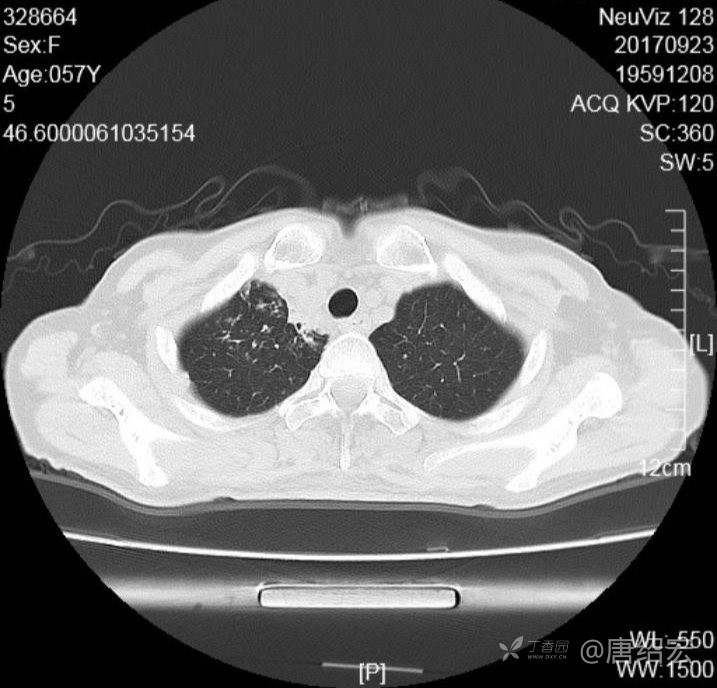

中年女性满肺树芽征还有支气管扩张,考虑什么疾病?

女,57岁,

主诉:发热、咳嗽、咯黄痰,胸闷3天入院。